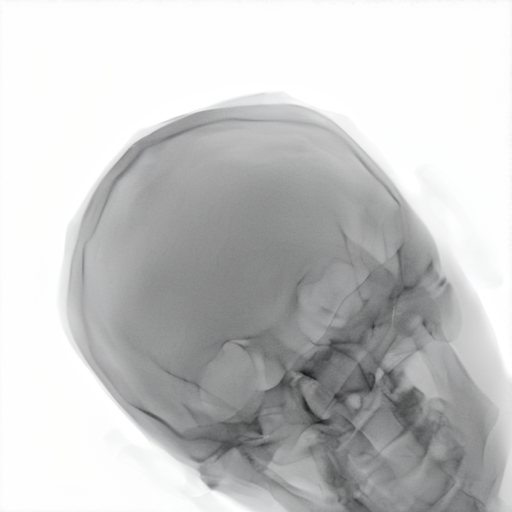

Table 4 shows more qualitative results that highlight how the denoising parameter τ\tau affects the style transfer process. When τ\tau is low, the model strongly pushes the images toward the target domain style. In some cases, especially at τ=0.3\tau=0.3, this leads to hallucinated structures that do not exist in the original image, similar to what we see with CycleGAN-Turbo. Although these outputs may appear visually plausible in the target domain, they no longer preserve the anatomy of the source, which is crucial in medical imaging.

As τ\tau increases, the outputs stay closer to the original structure. At midrange values like τ=0.5\tau=0.5, we get a good balance: the contrast in darker areas improves, the target style is seen, and the key structures are still intact. But if we go too far towards low τ\tau, some artifacts start to appear, like distorted soft tissue or over-sharpened edges.

5.3 Further evaluation of the translated X‐rays

The translated radiographs in Table 4 replace the sharp and unnatural edges of the synthetic skull with smoother gradients that resemble the natural variation found in real X-rays. The skull contours become more realistic, showing a gradual transition at the edges rather than the artificial, razor-sharp boundaries typical of forward-rendered projections. Inside the skull, subtle intensity variations appear, following anatomical structures such as sinus cavities and internal bone texture, especially visible in Samples 3 and 4. In general, brightness is slightly reduced and contrast is improved, making the images visually closer to real clinical scans.

The model also recovers soft tissue details that are missing in the synthetic images, such as the thin scalp and the fat layer surrounding the skull. These are rendered with more realistic transitions and shading, especially near curved regions. At the boundary between bone and soft tissue, the model produces smooth transitions that mimic how real imaging systems blur the interface. Deeper regions such as the mastoid and neck base show more natural transparency and layering, leading to richer contrast and a more authentic appearance. Although the translated images exhibit markedly improved realism, some domain discrepancies persist, which may reflect both the inherent limitations of current translation methods and the need for higher-fidelity synthetic inputs.